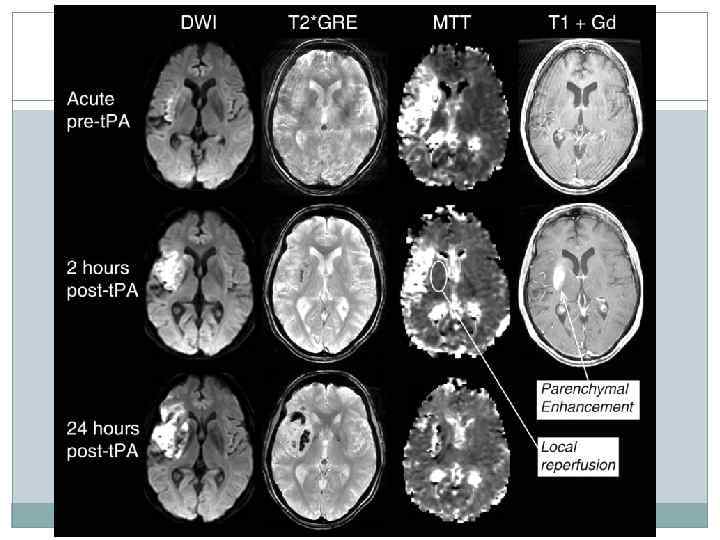

Начало заболевания неизвестно, в т. ч. симптомы развились после ночного сна (Wake-up ischemic stroke (WUIS), No last known well time stoke ) Использование перфузионного КТ или МРТ для определения острейшей фазы ишемического инсульта Критерии оценки для МРТ: гиперинтенсивность в DWI режиме при отсутствии гипоинтенсивных изменений на Т 2 и FLAIR. Критерии оценки для перфузионного КТ: ↓ церебрального кровотока (CBF), ↓ церебрального объема крови (CBV) и ↑ среднего времени прохождения крови (MTT) по сравнению с симметричными участками противоположного полушария